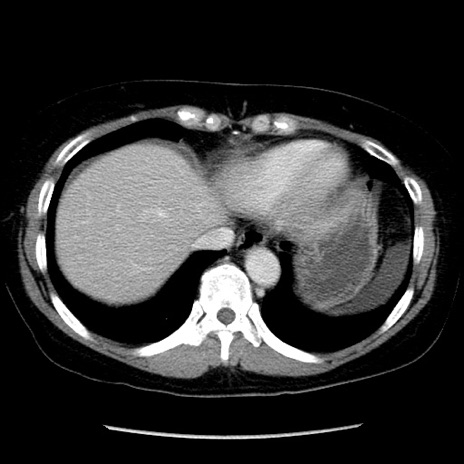

症例6(横断像)

【症例】50歳代女性

【主訴】下腹部痛

【現病歴】本日朝より下痢2回あり。 昼食を食べた後、嘔吐3回、下腹部痛認め、症状軽快せず、当院救急搬送。

最終食事:本日昼(生ものなし)。 昨日の夜、刺身を食ぺたとのこと。周囲に同様の症状の者なし。普段、排便は毎日あるとのこと。

【既往歴】卵巣癌術後(8年前に当院で卵巣摘出)

【身体所見】 意識清明、腹部:平坦、腸蠕動音→、やや硬、下腹部自発痛・圧痛あり、反跳痛あり、筋性防御なし。

【データ】WBC 16000、CRP 0.01